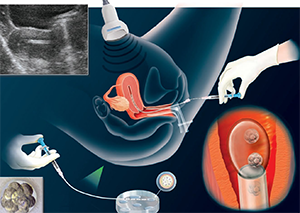

Egg Collection (Oocyte Pick Up)

At the end of the stimulation period, the egg collection can be performed under general anesthesia. This procedure is performed through vagina and under the guidance of ultrasound. A thin needle is introduced into the vagina and into the ovaries, and the follicles that harbor the eggs are aspirated. This fluid is brought to laboratory to pick up the eggs.

The classical in vitro fertilization (IVF) is performed by adding medium containing sperms into the micro chamber, where the eggs are stored. Sperms fertilize the eggs in a natural way. We use mostly ICSI procedure, where a single sperm is chosen and injected into the egg using an instrument called micromanipulator.

Embryos are transferred into the uterus usually between day 3 and 5 after egg collection after they are kept in culture medium as shown above.

Embryo transfer is asimple and painless procedure that is performed without anesthesia or sedation. The embryos are loaded into a thin plastic catheter, that is then introduced into the uterus via cervical canal. The number of embryos transferred depends on age of the woman, the previous attempts and the embryo quality.